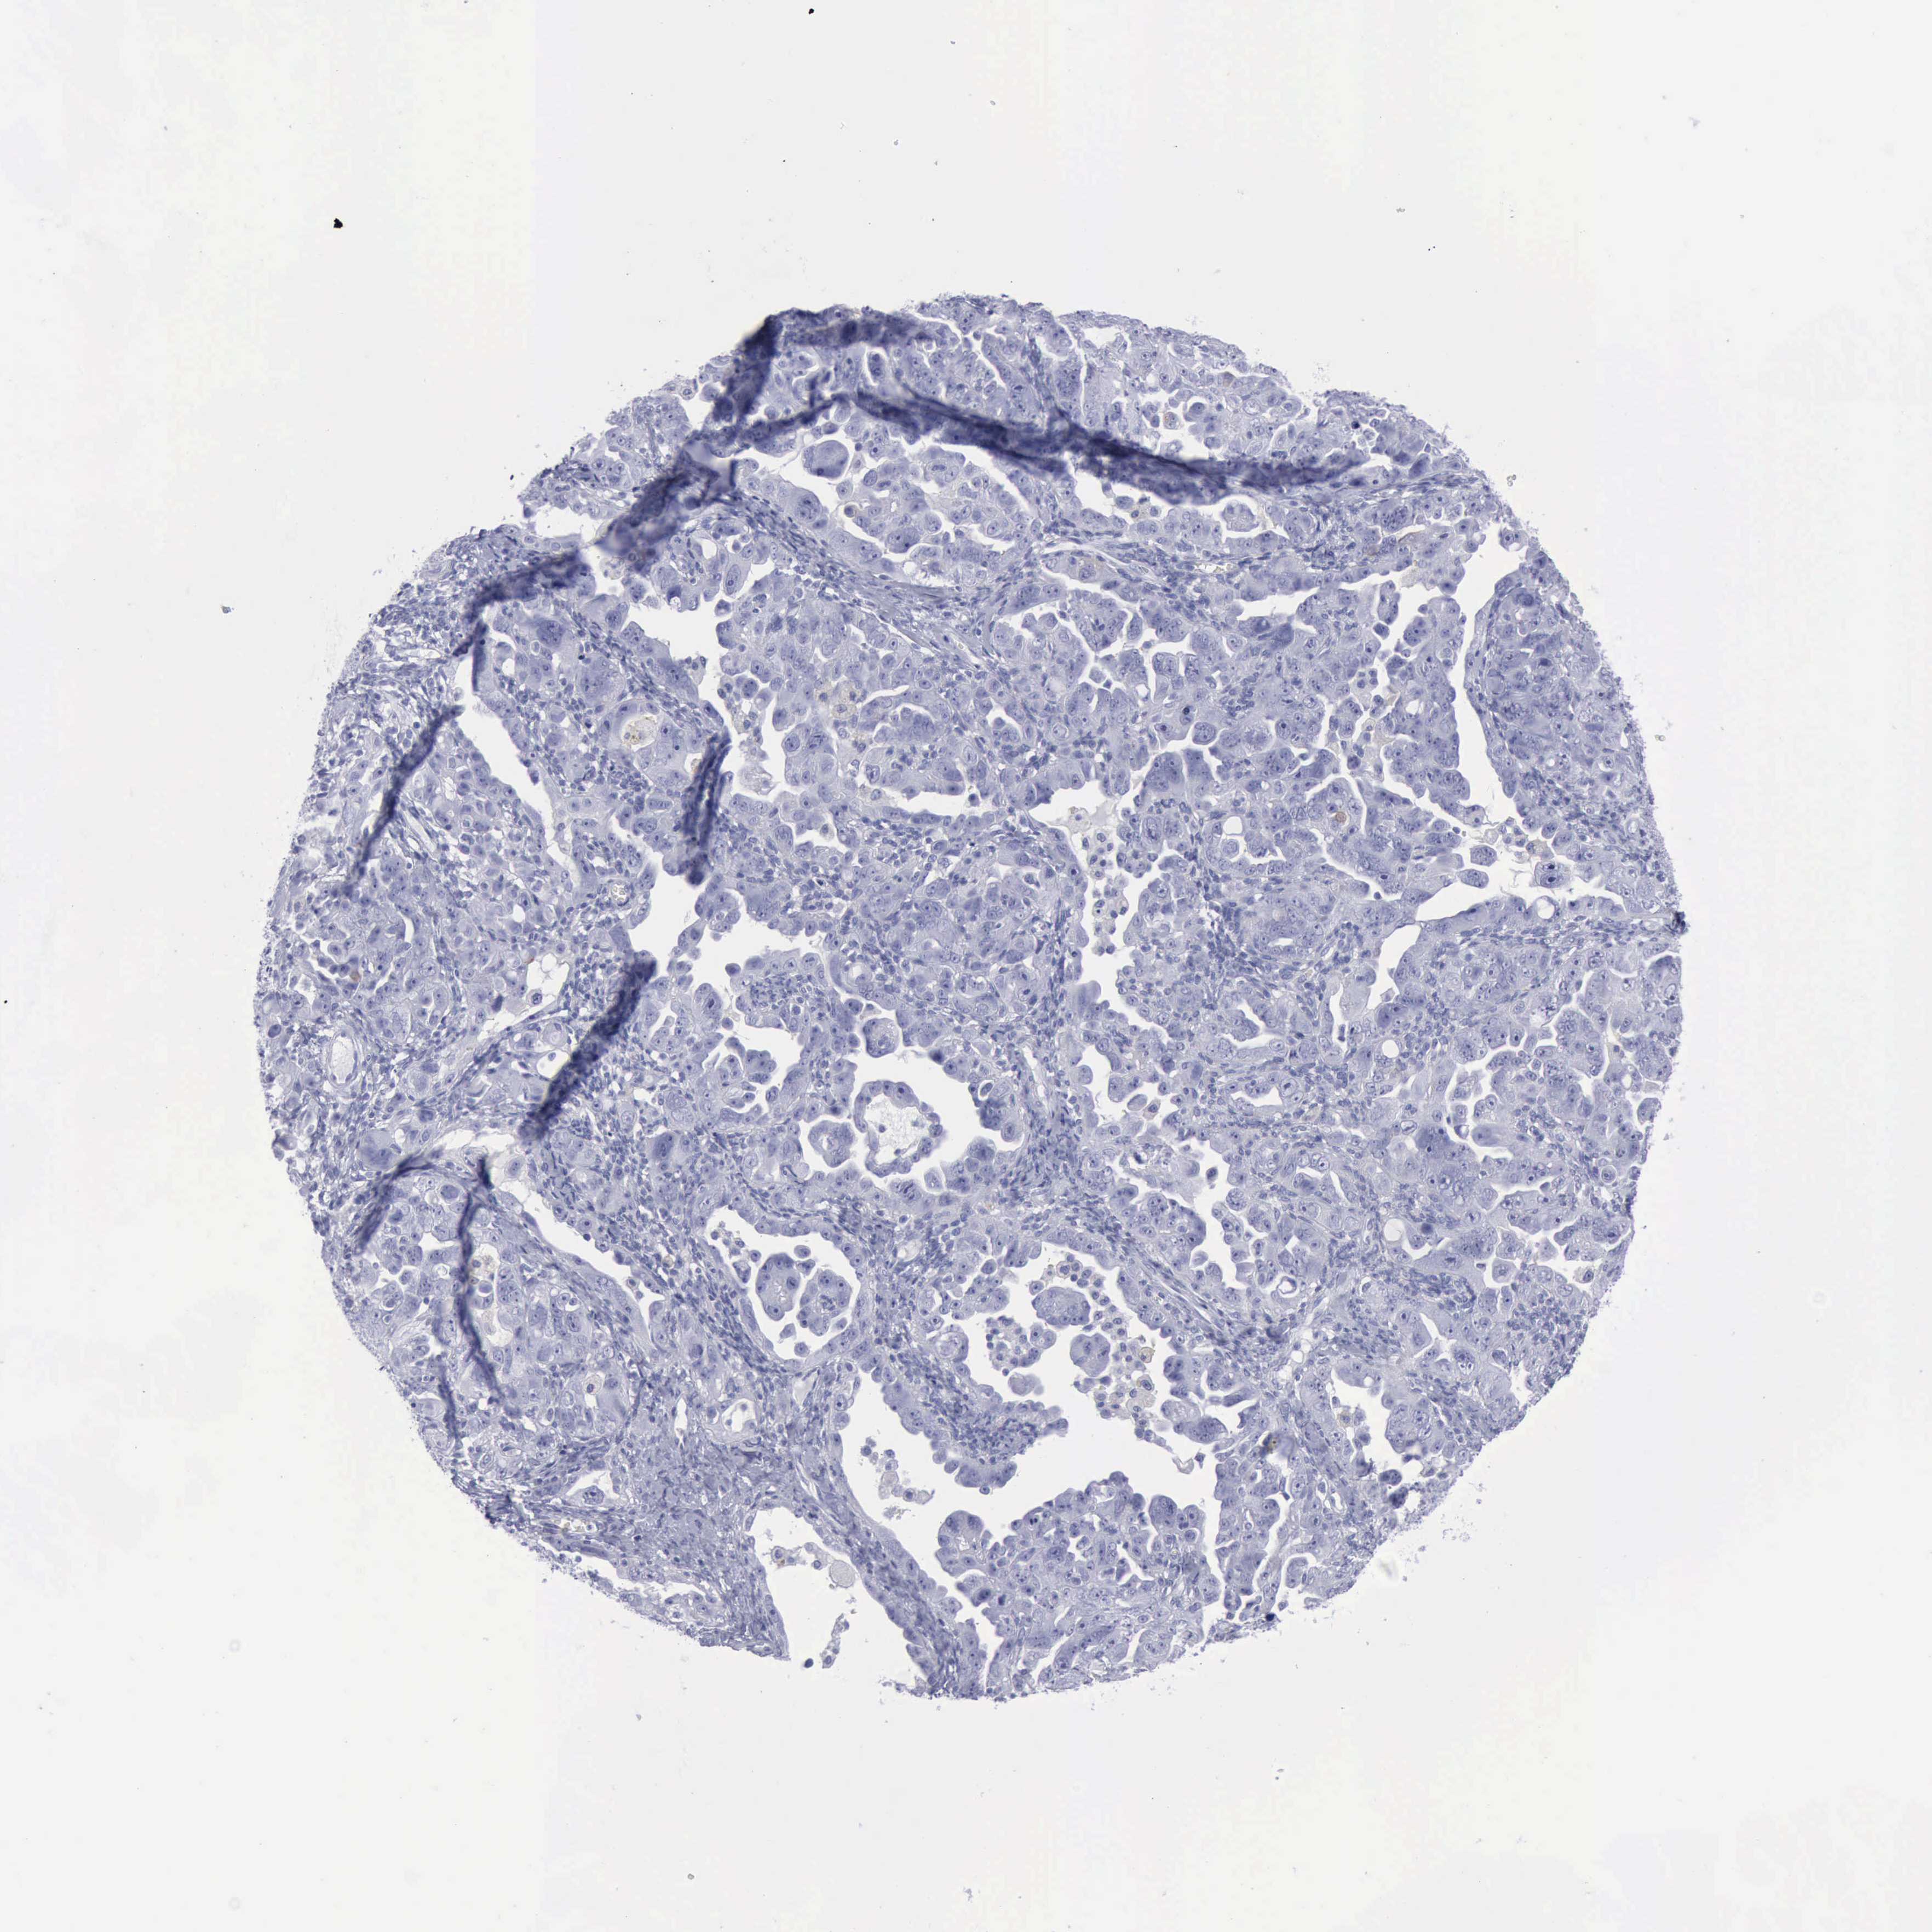

OVARIAN CANCER - Protein expressioni

A mouse-over function shows sample information and annotation data. Click on an image to view it in a full screen mode. Samples can be filtered based on level of antibody staining by selecting one or several of the following categories: high, medium, low and not detected. The assay and annotation is described here.

Note that samples used for immunohistochemistry by the Human Protein Atlas do not correspond to samples in the TCGA dataset.

Antibody stainingi

Antibody staining in the annotated cell types in the current human tissue is reported as not detected, low, medium, or high, based on conventional immunohistochemistry profiling in selected tissues. This score is based on the combination of the staining intensity and fraction of stained cells.

Each image is clickable and will lead to virtual microscopy that enables deeper exploration of all samples and also displays staining intensity scores, fraction scores and subcellular localization as well as patient and tissue information for each sample.

Antibody HPA030877

Antibody CAB000133

Staining

High

Medium

Low

Not detected

Intensity

Strong

Moderate

Weak

Negative

Quantity

>75%

75%-25%

<25%

None

Location

Nuclear

Cytoplasmic/membranous

Cytoplasmic/membranous,nuclear

Cystadenocarcinoma, serous, NOS